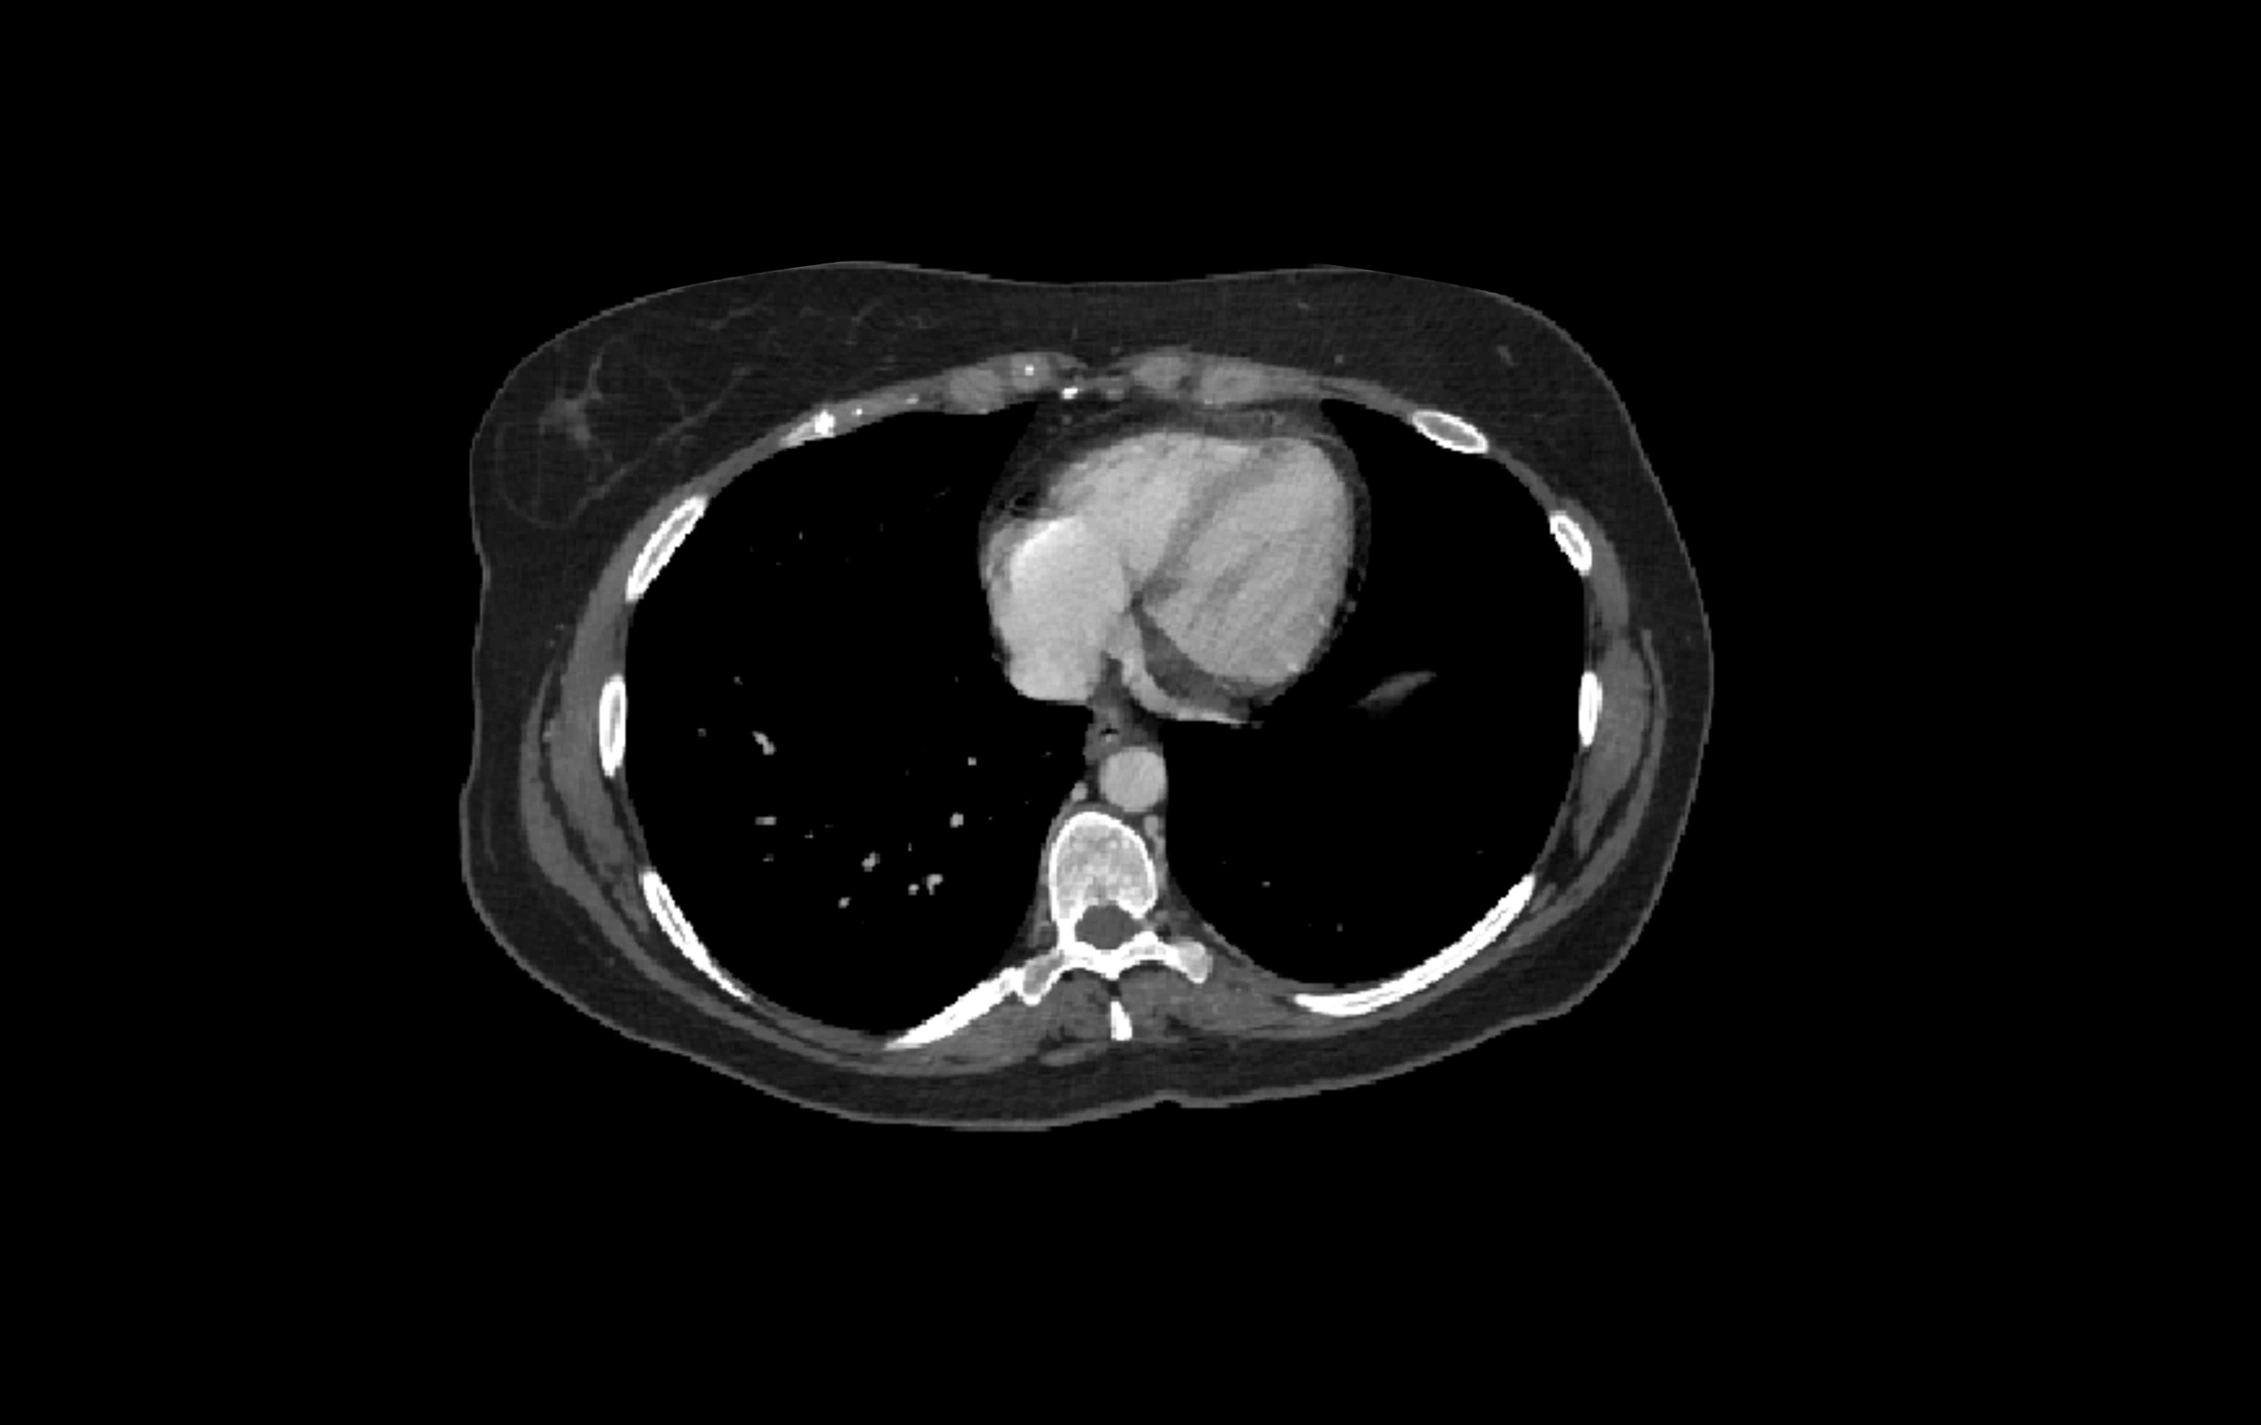

CT Appearance

CT Pre-Contrast:

• Caudate lobe appears as a soft-tissue density, isodense to the rest of the liver

• Enlargement may be appreciated in cirrhosis or Budd–Chiari syndrome

CT Post-Contrast:

• Homogeneous enhancement in the portal venous phase, similar to rest of liver

• Independent venous drainage into the IVC may be visualized

• Lesions follow characteristic CT enhancement patterns (HCC: arterial hyperenhancement with washout; hemangiomas: peripheral nodular enhancement with centripetal fill-in)

CT Venous Phase (functional significance):

• Caudate lobe often enhances relatively more than other lobes in Budd–Chiari syndrome, due to preserved venous outflow